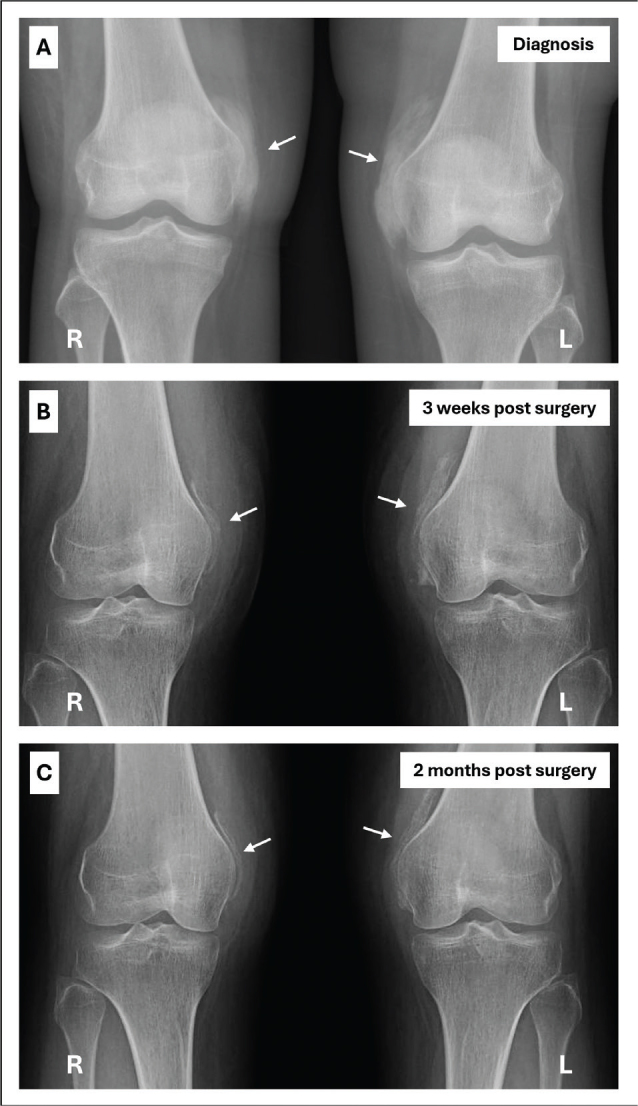

Case presentation: This case describes a young woman with no relevant previous medical history who developed severe bilateral heterotopic ossification on the anteromedial sides of her knees after an intensive care unit stay. Passive flexion of both knees was limited to 50°. X-ray was a simple diagnostic tool. Predisposing factors were extended immobilization, prolonged systematic inflammatory condition and mechanical ventilation. Due to the failure of initial conservative therapy, the heterotopic ossification was resected early, 4 months after onset of first symptoms. Following an intensive rehabilitation program, a normal, pain-free gait and full range of motion of both knees were achieved 9 months after surgery.